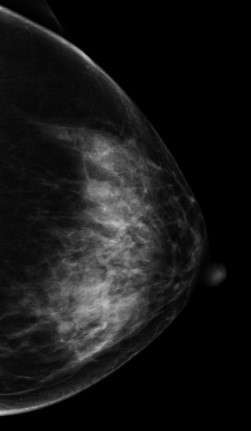

V-preview图像:

影像描述: 常规2D图像MLO位左乳腺内见多个小结节影,下象限似见一团块影,边界模糊,CC位上并没有发现异常团块影,在V-Perview图像MLO位下象限见一类圆形团块影,部分边界尚清,但CC位上并没发现明显异常团块影,DBT断层图像在MLO和CC位上左乳内下象限清晰可见类圆形致密影,其边缘光滑锐利。 影像诊断: 左侧乳腺多发良性结节,BI-RADS 3。 病例点评: 最后病理证实纤维腺瘤,类似这样病例DBT可以给我们提供更多诊断信息有助于明确病变性质。